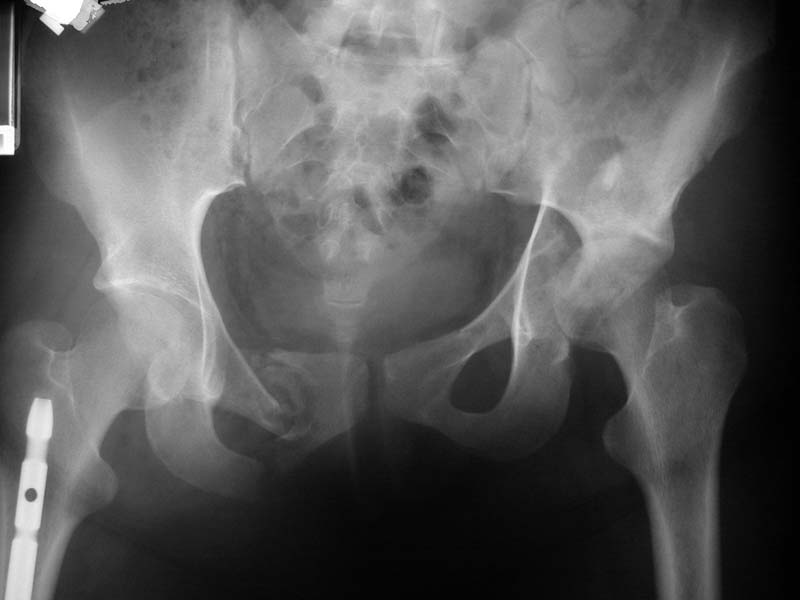

19 year old girl 3 weeks out from injury. Femur, tibia, ankle and patella fractures all fixed at an outside hospital. Her pelvic fracture and acetabular fracture were treated in tractionuntil she was transferred to Parkland.

How would you treat this one?